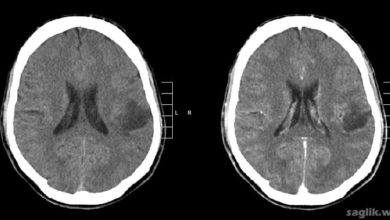

Gliom (glioma), beyin ve omurilikte ortaya çıkan bir tümör türüdür. Gliomalar, sinir hücrelerini çevreleyen ve işlev görmelerine yardımcı olan destekleyici…